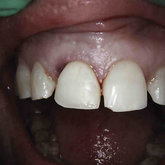

Porcelain crowns and restorations made in one appointment.

We make it a priority to incorporate the latest in dental technology in everything we do at our practice. ...